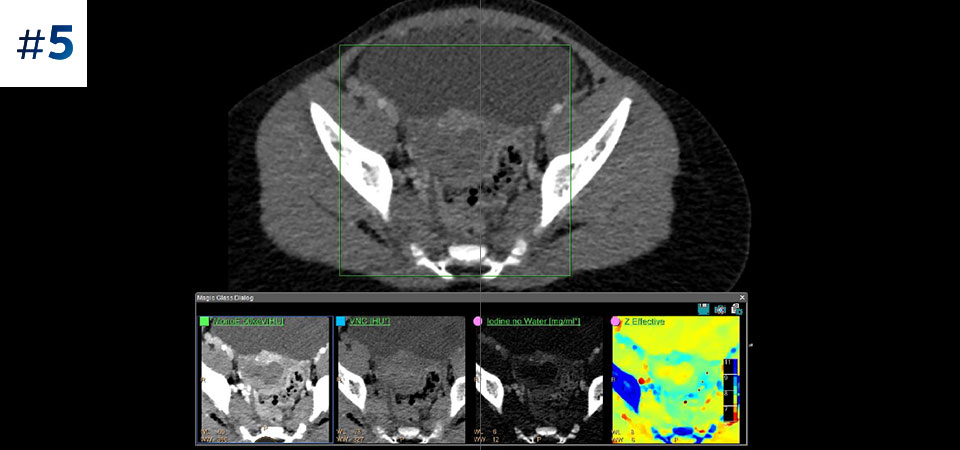

Vá além da CT convencional. Veja de que forma os vários tipos de resultados obtidos com deteção espectral podem aumentar a fiabilidade do seu diagnóstico.

Redução do número de exames de seguimento Uma melhor caracterização dos tecidos poderá reduzir a necessidade de novos estudos follow-up no caso de exames incompletos ou inconclusivos.